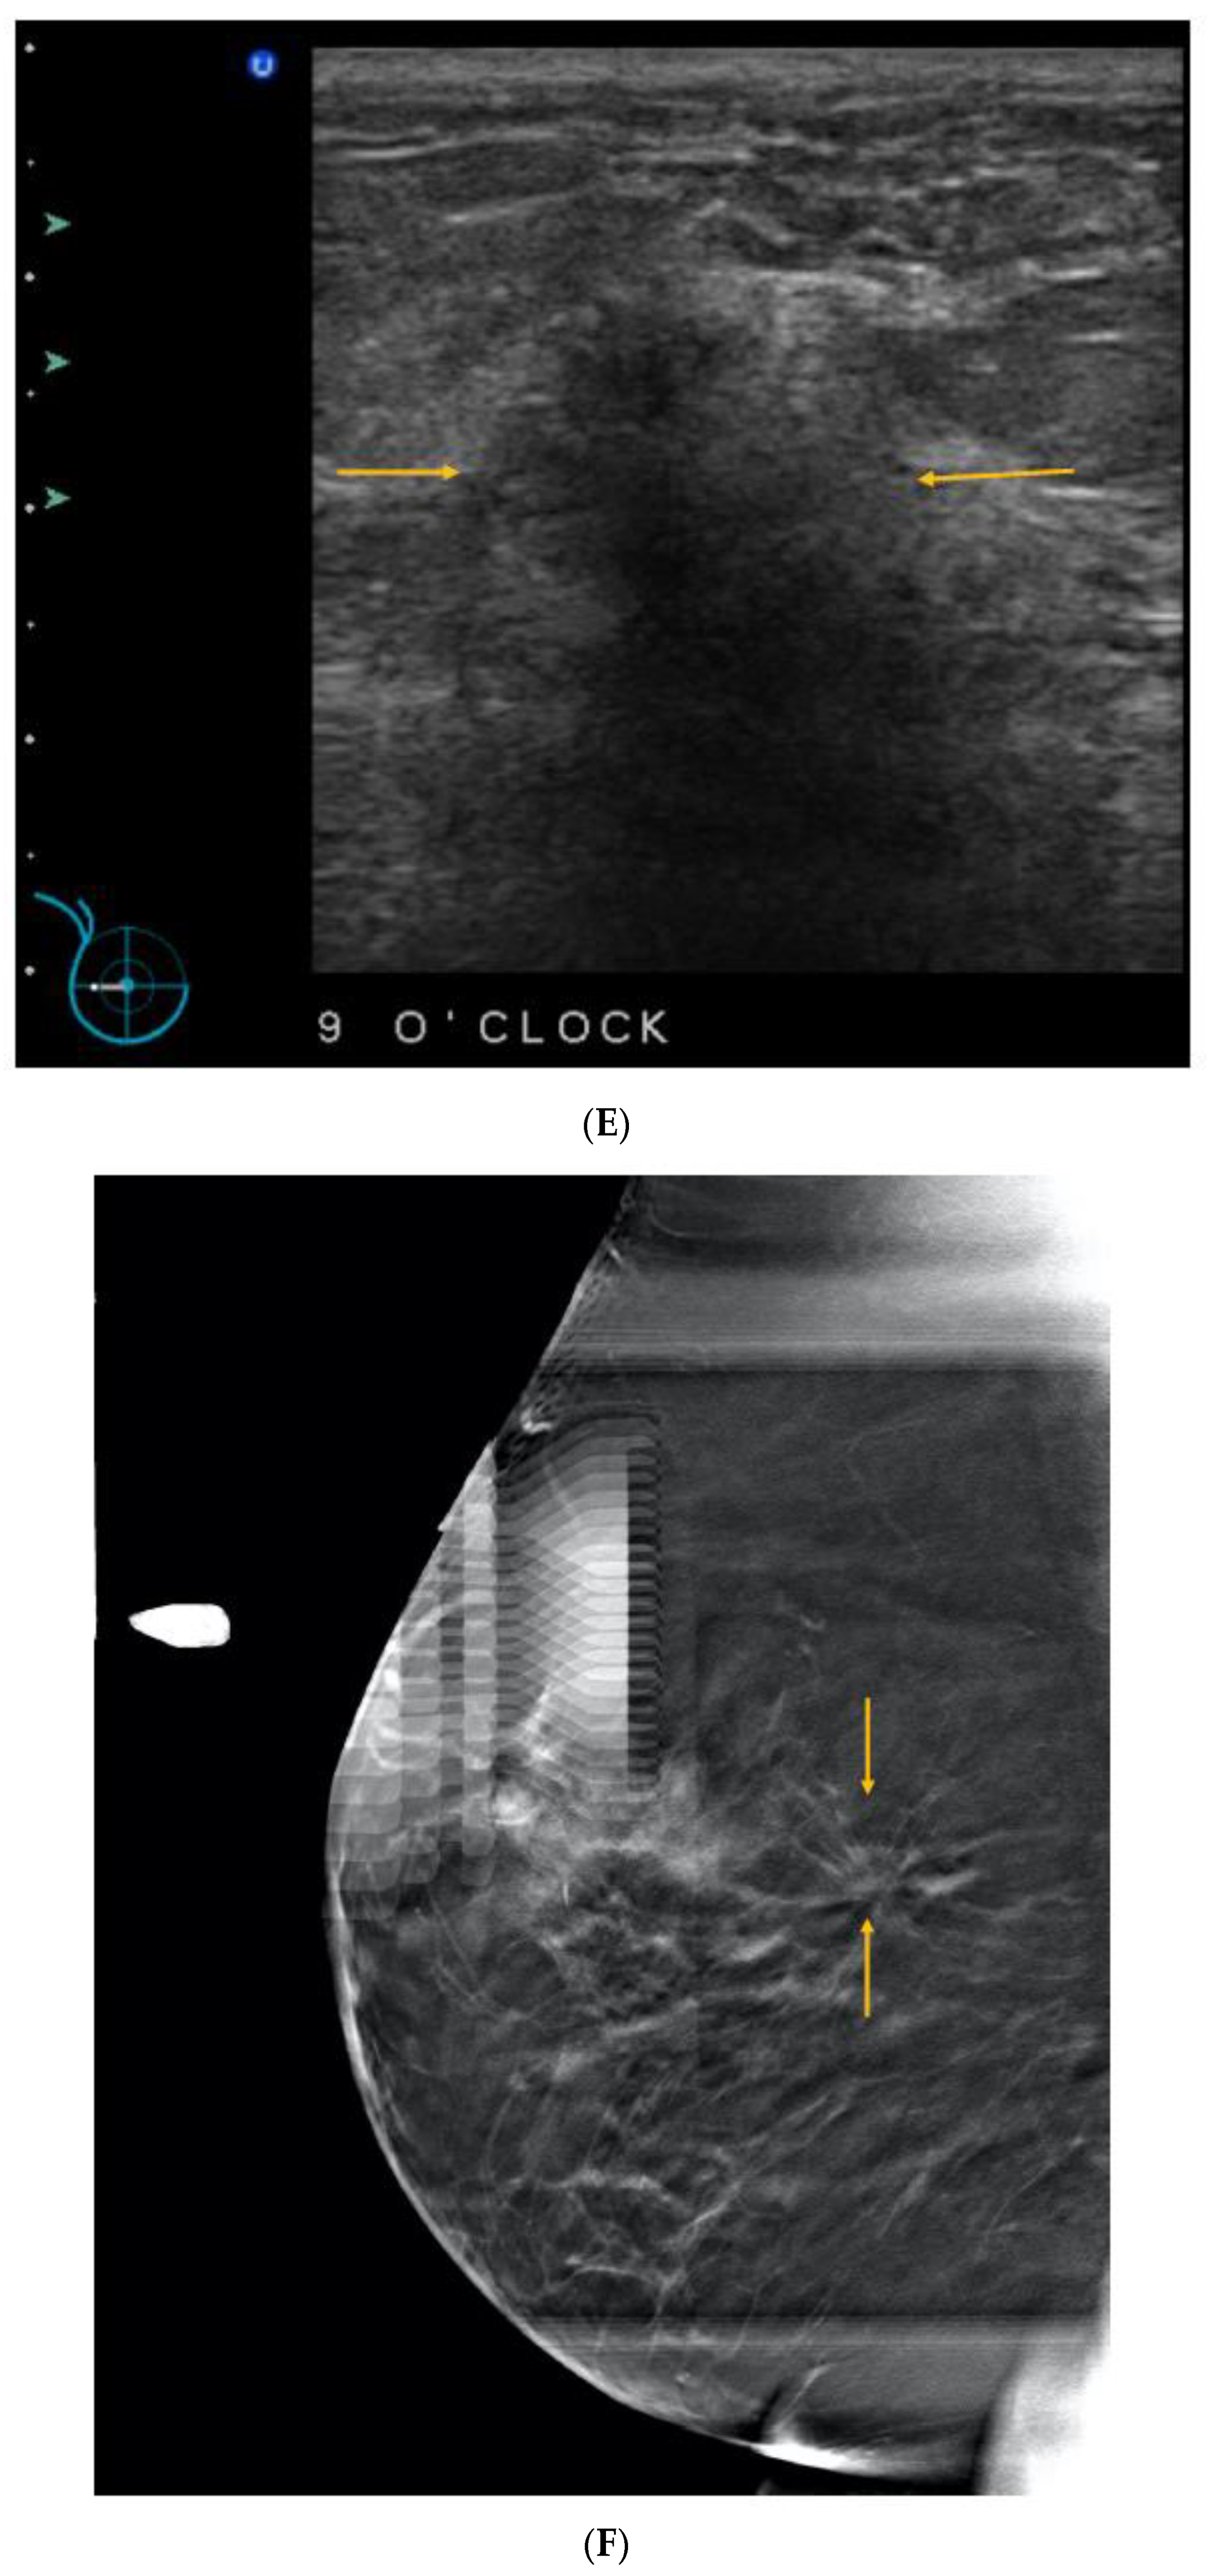

5. Ultrasound (US)